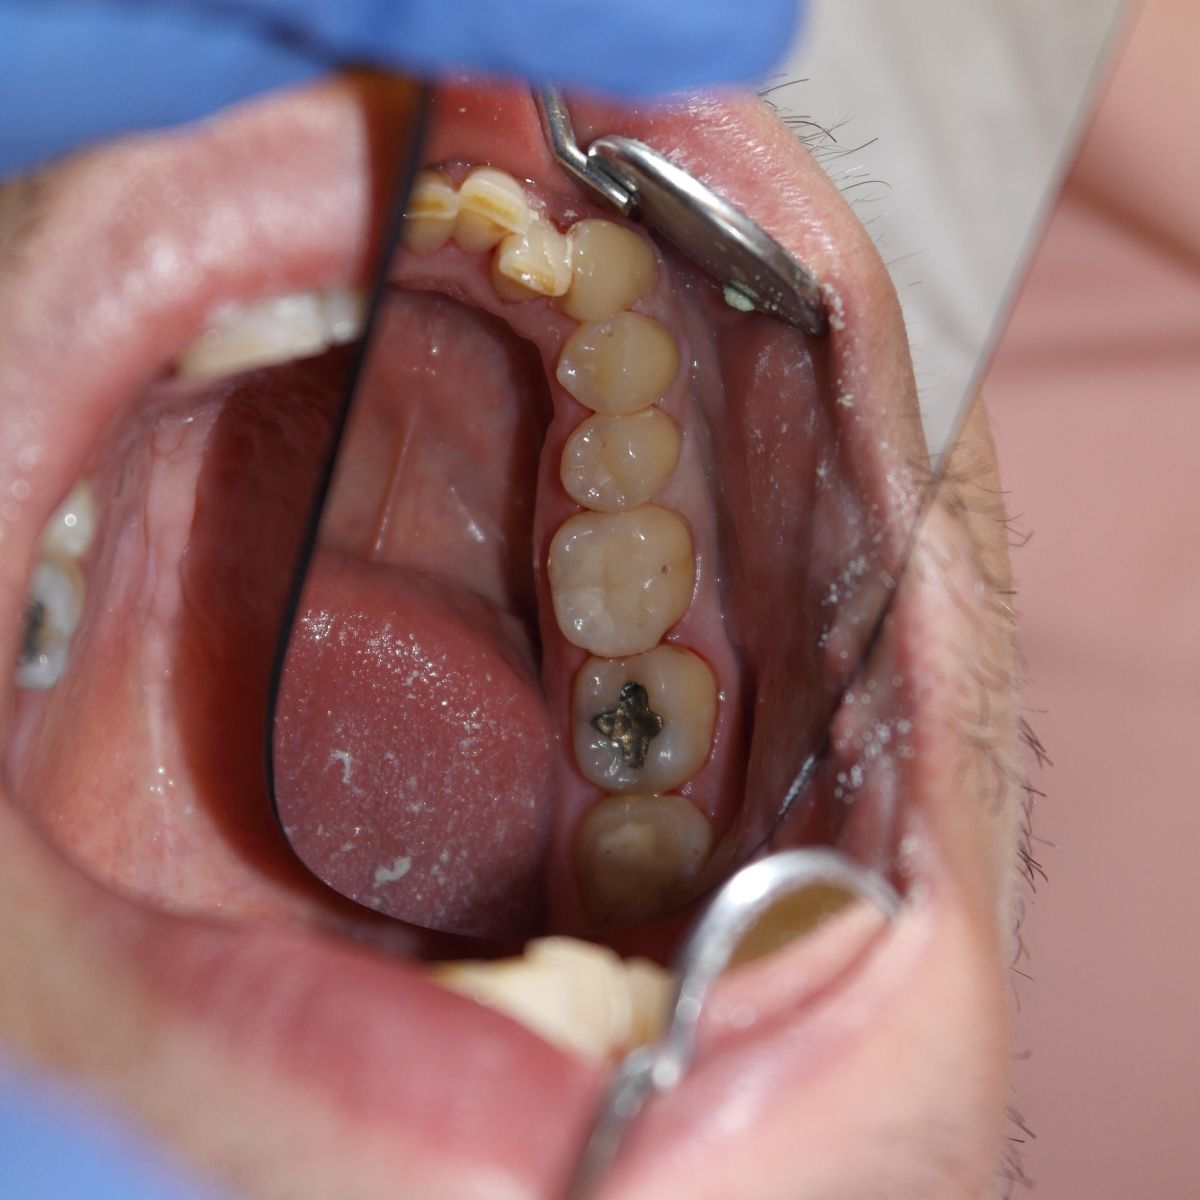

A fogászatban tömés alatt azt a műveletet értjük, mely során különböző anyagok fogba helyezésével helyreállítjuk a sérült fog egységét. A fog tömése fúrással kezdődik, amikor is a fogorvos feltárja a szuvas részeket, és megtisztítja az érintett részeket. Az így keletkezett lyukat tölti ki a fogtömő anyaggal.

Töméskor tehát a szuvas részt mindenképpen el kell távolítani, ezután tömhető be a lyuk, amelyre többféle anyag is használható:

Előfordul, hogy ha a foganyag nagyobb része szuvas, már nem lehet töméssel helyreállítani a fog szerkezetét, ilyenkor fogtechnikai laborban készített betéteket alkalmazunk.

Kisméretű kerámia szemcsék segítségével erősített kompozitból áll, melyek a természetes fogak színével megegyeznek és jó a kopásállóságuk. Legtöbbször fogszuvasodás miatt károsodott fogaknál vagy amalgám tömés eltávolítását követően használjuk. Élettartama általában 10 év.